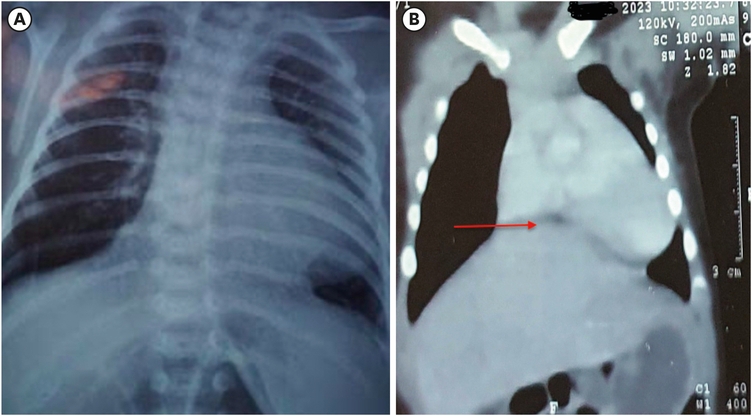

The five-week-old male child was referred to our institute for CHD with respiratory distress for one week. The child was preterm and born by cesarian section because of placenta previa and, had a smooth perinatal period, and had no complaints till four weeks of age. He suddenly developed respiratory distress and attended a local hospital where the child was intubated and kept on a ventilator. On further investigations, the X-ray chest showed an enlarged heart shadow, and echocardiography (2D echo) was reported as a hypoplastic right ventricle inlet. Afterward, he was referred to our institute for further management. After primary resuscitation, a chest radiograph was done, which depicted a slightly enlarged heart shadow and clear lung fields (Fig. 1A). A 2D echo was done, suggesting an external mass compressing on the right ventricle and possibly causing inflow tract obstruction. No other structural anomaly was detected; the right ventricular outflow tract and pulmonary pressures were normal. A CT scan was done to delineate the anatomy more clearly, which showed herniated liver tissue anterior to the pericardium and compressing it, suggesting MH (Fig. 1B).

Fig. 1

Radiological investigations. (A) An X-ray of the chest showing a slightly enlarged heart shadow and mediastinal shift to the left side. (B) Computerized tomography reconstructed coronal image showing herniation of the liver (red arrow) into the thoracic cavity and compression on the pericardium.